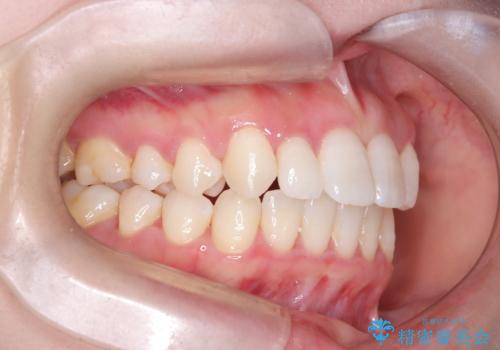

- 歯のデコボコと右上2番の歯の形が気になることを主訴に来院された患者様です。

軽度の叢生(凸凹)であったため、インビザラインのライトパッケージを用いて歯並びを改善しました。その後、右上2番はオールセラミッククラウンにより形態を回復し、審美性を向上させました。

歯並びと見た目がきれいになり、治療も短期間で終わったことから、患者様にも大変ご満足いただきました。